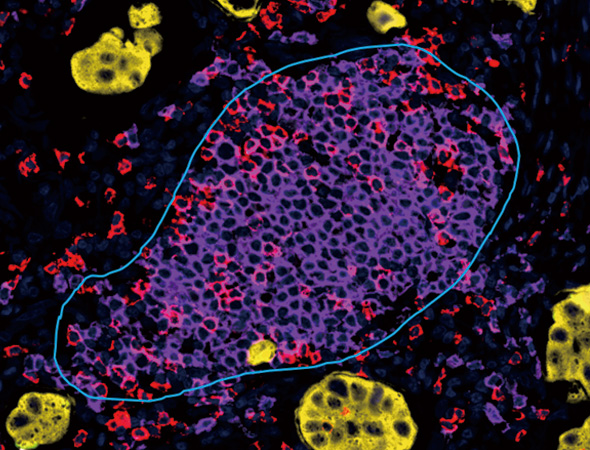

Nucleus, PD-1,Pan-CK

根据肿瘤蛋白标记或组织形态将组织划分为肿瘤实质区和间质区,并统计组织区域面积、阳性细胞数量、百分比、密度。

通过识别组织图像中标志物的染色信息,自动调节荧光强度并识别出图像中 TLS 结构进行标注,进一步定量分析可得到图像中每个 TLS 独立的定量数据,同时可进一步对三级淋巴结构的内部进行空间分析。